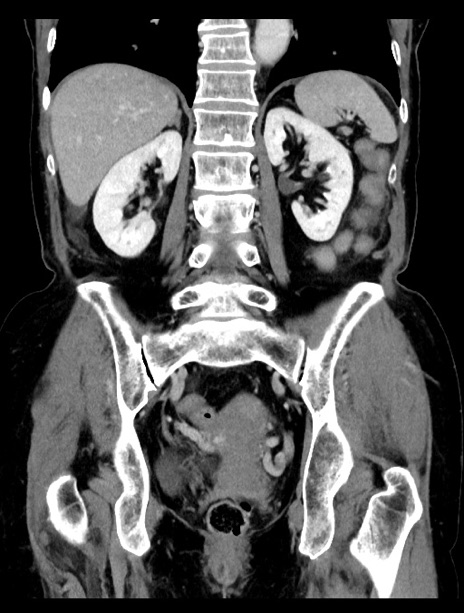

症例23(冠状断像)

【症例】70歳代女性

【主訴】下腹部痛・嘔吐

【現病歴】2日前より腹痛あり。昨日嘔吐あり。症状改善しないため来院。

【既往歴】胃GISTに対して胃部分切除後。

【身体所見】BT 37.1℃、BP 128/77mmHg、腹部:平坦・軟、下腹部に圧痛あり。

【データ】WBC 10200、CRP 0.31